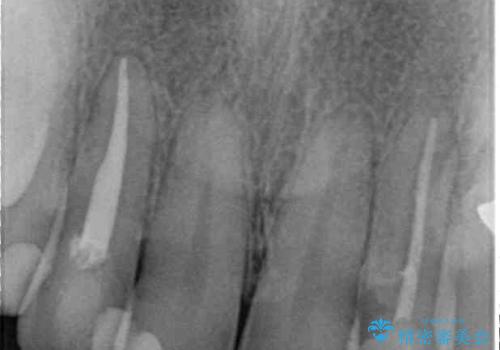

- 前歯の歯並びと神経を取って変色してしまった前歯を気にして来院された患者様です。

上下前歯の歯列不正はインビザラインにより整え、その後に、前歯2本をオールセラミッククラウンにて補綴治療することとしました。

下顎前歯が1本欠損しており、下顎歯列の大きさが本来よりも小さいため、上顎歯列とのバランスが悪く、深い咬み合わせになっていました。

上顎にIPRを多用して歯列の大きさを小さくするよう試みましたが、理想的な咬み合わせまでには改善させることはできませんでした。